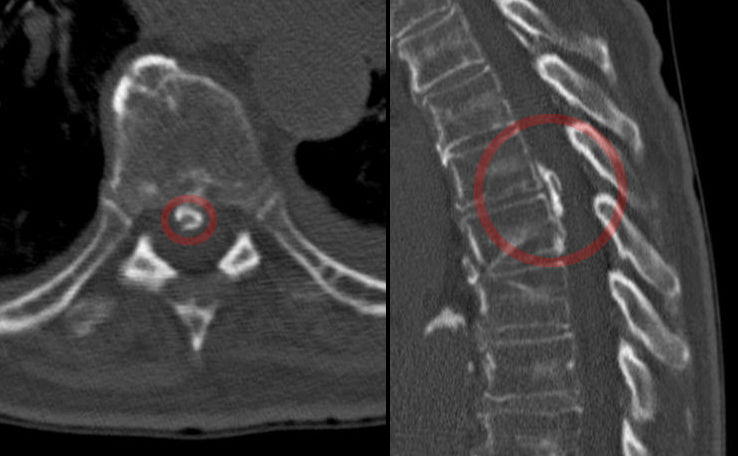

Your medical professional might additionally recommend a series of imaging treatments to establish the source of your pain in the back. These imaging procedures can include x-rays, bone scans, as well as CT scans. These imaging procedures can be handy, yet they aren't always needed for a lot of instances of neck and back pain. If you have extreme pain in the back, your medical professional may recommend a shot. These injections can aid to ease discomfort and minimize inflammation.

If you have actually a pinched nerve in lower back, your doctor will certainly do a physical examination to identify the reason. If your medical professional is uncertain of the reason, she or he might get imaging tests. These examinations can detect nerve origin compression and assistance to determine the degree of the damages. You can additionally have spinal injections to soothe the discomfort as well as swelling. Your doctor might likewise recommend you dental or injected corticosteroids if your various other therapies have not functioned. If you have diabetics issues, you are at greater threat for establishing nerve compression. You ought to prevent repeated activities that strain your back and also ought to additionally add stamina exercises to your regular workout routine.